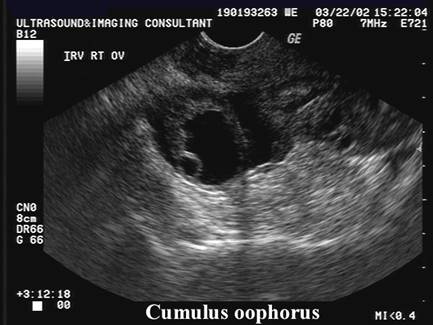

OVULATION

Baerwald et al (4) characterized changes in luteal form and function using serial transvaginal ultrasonography, gray-scale imaging and analysis of serum hormonal patterns. The hypothesis that changes in luteal morphology and endocrine secretion would be detected during the interval between two subsequent ovulations seems to be supported.

Two morphological types of CL were observed following ovulation:

·         with a central fluid-filled cavity (CFFC) (78%),

·         without a central fluid-filled cavity (CFFC).